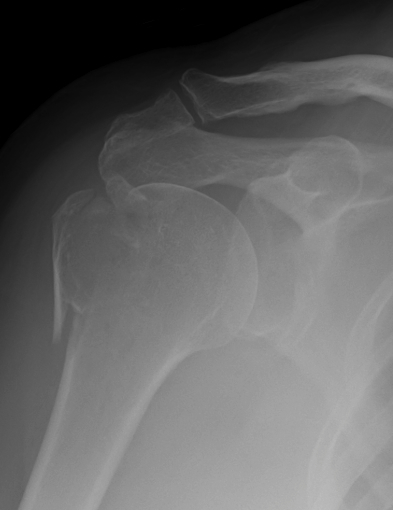

Xray / CT

Deforming force - rotator cuff displaces superiorly (supraspinatus) and posteriorly (infraspinatus)

Look for occult surgical neck of humerus fractures